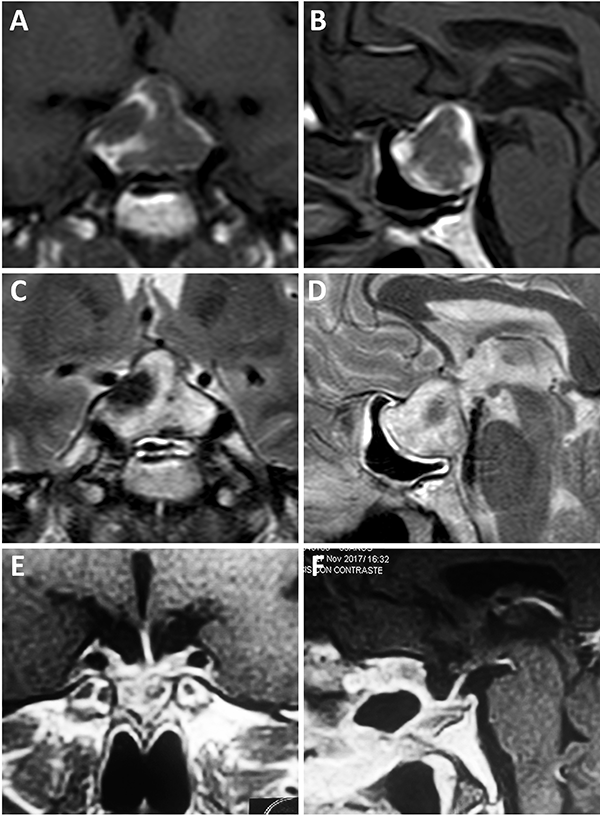

Resonancia magnética

El método gold standard para el diagnóstico imagenológico de un adenoma de hipófisis es la RM. Ese estudio nos servirá también para planificar el abordaje, clasificar el tumor, objetivar estructuras aledañas, predecir resultados postoperatorios y riesgo de complicaciones.11,30,34,41

En relación a los microadenomas, en ocasiones pueden ser dificultosos de hallar en un estudio de baja calidad o sin secuencias dinámicas. Inclusive del 20 al 50% de los adenomas secretores de ACTH pueden no ser visibles en estudios.27 En este sentido, las secuencias dinámicas ayudan a esclarecer la ubicación del tumor.

Una clasificación clásica de los adenomas es según su tamaño. Se los clasifica en microadenoma <10 mm (fig. 2), macroadenoma >10 mm (fig. 3), y adenoma gigante > 30 mm (fig. 4). Esta clasificación es importante ya que los índices de remisión están ligados al tamaño del adenoma y también su recidiva.12

Figura 2: Microadenoma. A-B: RM preoperatoria; C-D: RM postoperatoria.

Figura 3: Macroadenoma. A-B: RM preoperatoria; C-D: Campo visual preoperatorio; E-F: RM postoperatoria; G-H: Campo visual postoperatorio.

Figura 4: Adenoma gigante. A-B: RM preoperatoria; C-D: RM postoperatoria.

Clasificación de Knosp

En 1992 Knosp et al. publicó una clasificación para cuantificar la invasión del seno cavernoso (Tabla 3). Esta clasificación evalúa la extensión paraselar tomando como referencia la arteria carótida del lado a evaluar. Se elige un corte coronal de RM donde se visualiza la porción supracavernosa e intracavernosa, se traza una línea intercarotídea y se categoriza al paciente según el grado de invasión del adenoma del grado 0 al 4 (fig. 5).34

Figura 5: Adenomas hipofisarios Knosp grado 4. A-D: Obsérvese el englobamiento carotídeo.

Barrera selar

El techo de la fosa pituitaria está constituido en condiciones normales por un máximo de 2 estructuras: duramadre (diafragma selar) y aracnoides.65,66 En condiciones patológicas, cuando existe un adenoma hipofisario, éste empuja hacia arriba a la glándula. De este modo, la interfase entre el tumor y el LCR se encuentra constituida por un máximo de 3 elementos: glándula, duramadre y aracnoides. Cabe destacar que la aracnoides es el único elemento constante. A los elementos que constituyen esta interfase el equipo de Tucumán los denominó “barrera selar”.11,60

Existen 3 subtipos de barrera selar según los hallazgos intraoperatorios, luego de resecar el tumor:

Un factor interesante de este novedoso concepto es que el tipo de barrera puede evidenciarse en la RM preoperatoria. De este modo, existen 3 subtipos de barrera selar según la radiología:

Los pacientes con una barrera débil tienen mayor riesgo de fístula intraoperatoria de LCR. La barrera fuerte es un factor protector de fístula de LCR.11,60

Figura 6: Barrera selar fuerte. A-B) RM preoperatoria. C-D) Hallazgos intraquirúrgicos. E-F) RM postoperatoria. Flechas amarillas: interlinea > 1mm. Tomado de Campero A, Villalonga JF, Basso A. Anatomical risk factors for intraoperative cerebrospinal fluid leaks during transsphenoidal surgery for pituitary adenomas. World Neurosurg. 2019;124:346-55.

Figura 7: Barrera selar mixta. A y C) RM preoperatoria corte coronal; B y D) RM preoperatoria corte sagital; E-F) Hallazgos intraoperatorios; G-H) RM postoperatoria. Flechas y líneas: color rojo indican barrera débil; color amarillo indican barrera fuerte. Tomado deVillalonga JF, Ries-Centeno T, Sáenz A, Solari D, Cervio A, Campero A. The mixed sellar barrier: a new subtype of this novel concept. World Neurosurg. 2019;132:5-13.

Figura 8: Barrera selar débil. A-B) RM preoperatoria; C-D) Hallazgos intraoperatorios. E-F) RM postoperatoria. Flechas rojas: interlínea < 1mm. Tomado de Campero A, Villalonga JF, Basso A. Anatomical risk factors for intraoperative cerebrospinal fluid leaks during transsphenoidal surgery for pituitary adenomas. World Neurosurg. 2019;124:346-55.

Tomografía computada

Apoplejía

La conducta a seguir en la apoplejía pituitaria es controversial ya que no hay estudios comparativos sobre manejo conservador o quirúrgico (fig. 16). Actualmente se reconoce que el primer paso es el control hemodinámico, control electrolítico y administración con corticoides. Luego de este paso inicial, la cirugía es de elección si se reconoce que el paciente posee alteración de la conciencia que no revierte con corticoides o alteraciones visuales.62 Diferentes estudios demuestran mejores resultados en el compromiso tanto de la agudeza visual como en la motilidad extrínseca del ojo con el tratamiento quirúrgico hasta en un 60% de los casos. Otro punto importante es la recuperación de la función glandular, para la cual, la cirugía posee mejores resultados recuperando la función parcial o completamente hasta en un 60%.52,62 Otro argumento fuerte a favor de la cirugía es la posibilidad no solo de mejorar la función visual y glandular sino de generar la exéresis tumoral en el mismo acto. Se ha evidenciado una recidiva tumoral del 11% a 6 años.9

Figura 16: Apoplejía con resolución quirúrgica. A-B) RM preoperatoria, secuencia T1 con contraste; C-D) RM preoperatoria, secuencia T2; E-F) RM postoperatoria, secuencia T1 con contraste.